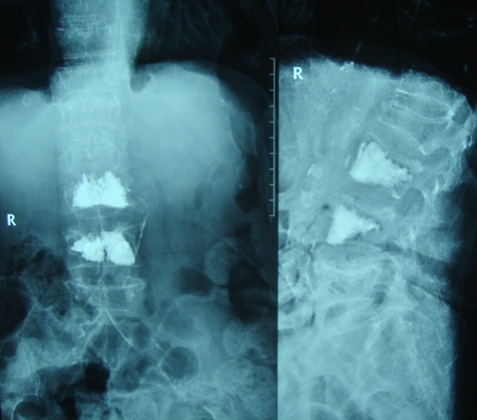

4、老年骨质疏松患者椎体发生压缩骨折有手术指征者。

图5.老年骨质疏松患者椎体压缩骨折椎体成形术后